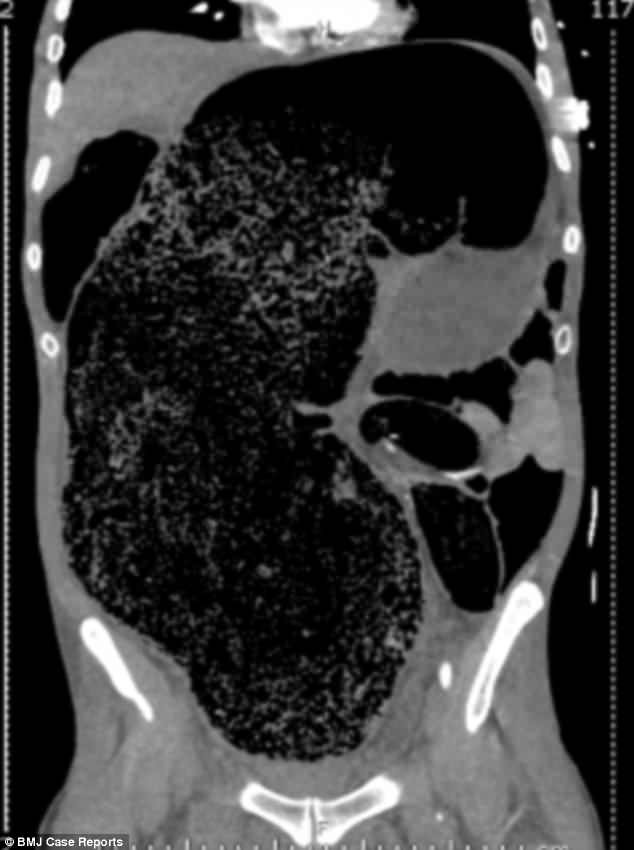

Hình ảnh chụp cho thấy số phân khổng lồ tích trong ruột bệnh nhân (Ảnh: Daily Mail)

Sau khi làm các xét nghiệm cần thiết và phát hiện khối lượng phân khổng lồ tích tụ trong đại tràng, các bác sĩ thực hiện thụt tháo hết số phân tắc nghẽn ra khỏi cơ thể bệnh nhân.

Theo chẩn đoán của các bác sĩ, khối lượng phân lớn tích tụ trong cơ thể này là nguyên nhân chính dẫn tới tình trạng đau đớn của bệnh nhân, bởi nó chèn ép các nội tạng xung quanh của người đàn ông như tăng áp lực lên dạ dày, làm tắc các mạch máu lưu thông xuống chân, làm tổn thương thận.